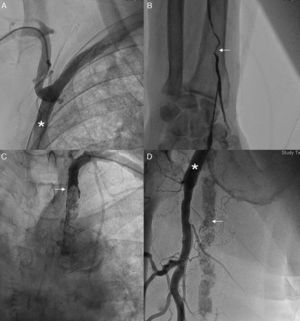

Los días previos a su ingreso hospitalario presentó un cuadro compatible con melenas. A su ingreso refiere epigastralgia y cortejo vegetativo, de 10h de evolución, evidenciándose en el electrocardiograma elevación del ST de 2mm en cara inferior, motivo por el que se le administró dosis de carga con ácido acetilsalicílico (300mg) y clopidogrel (300mg) vía oral, un bolo intravenoso de heparina sódica (5.000UI) y nitroglicerina intravenosa en perfusión continua. Sin embargo, y debido al cuadro reciente de sangrado digestivo se desestima la fibrinólisis, y se realiza una angioplastia primaria. Inicialmente se planteó el abordaje a través de la arteria radial derecha sin poder llegar hasta la aorta ascendente, debido a la gran angulación de la subclavia derecha tras la salida del bypass axilobifemoral (fig. 1A). Por la imposibilidad del acceso derecho, se intentó acceder a través de la arteria radial izquierda sin conseguirse, debido a estenosis a este nivel (fig. 1B). Por este motivo se canalizó la arteria braquial izquierda, sin conseguir llegar hasta la aorta, debido a la presencia de una suboclusión a nivel proximal de la subclavia izquierda (fig. 1C). Finalmente, se intentó la canalización de las arterias femorales, por debajo de la conexión del bypass axilobifemoral, y sin pinchar a estos, sin conseguirse la canalización arterial femoral (fig. 1D).

A) Evidencia de gran angulación de la subclavia derecha tras la salida del bypass axilobifemoral (asterico). B) Estenosis de la arteria radial izquierda (flecha). C) Suboclusión a nivel del tercio proximal de la subclavia izquierda (flecha). D) Gran calcificación a nivel de la arteria femoral superficial (flecha) con bypass axilofemoral (asterisco) conectado a la arteria femoral profunda.